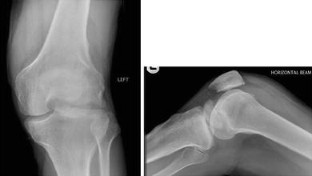

We report the case of an isolated, low energy, closed, displaced, lateral femoral condyle Hoffa fracture in a 54 year old Caucasian man. This was treated by open reduction and internal fixation using two headless compression screws. At 1 year review the patient was pain free, the fracture had radiographically united and there was a range of movement to his knee of 0°–100°.

Fig. 1